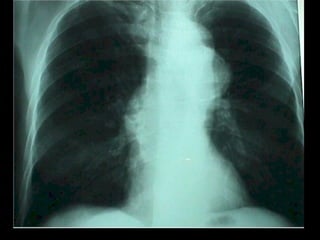

CARDIOMEGALIA GLOBAL Las causas más frecuentes son: Cardiopatía Reumática Plurivalvular Avanzada  Miocardiopatías Congestivas Diagnóstico Diferencial  Enf. De Ebstein Derrame Pericardico

CARDIOMEGALIA GLOBAL Lascausas más frecuentes son: Cardiopatía Reumática Plurivalvular Avanzada Miocardiopatías Congestivas Diagnóstico Diferencial Enf. De Ebstein Derrame Pericardico